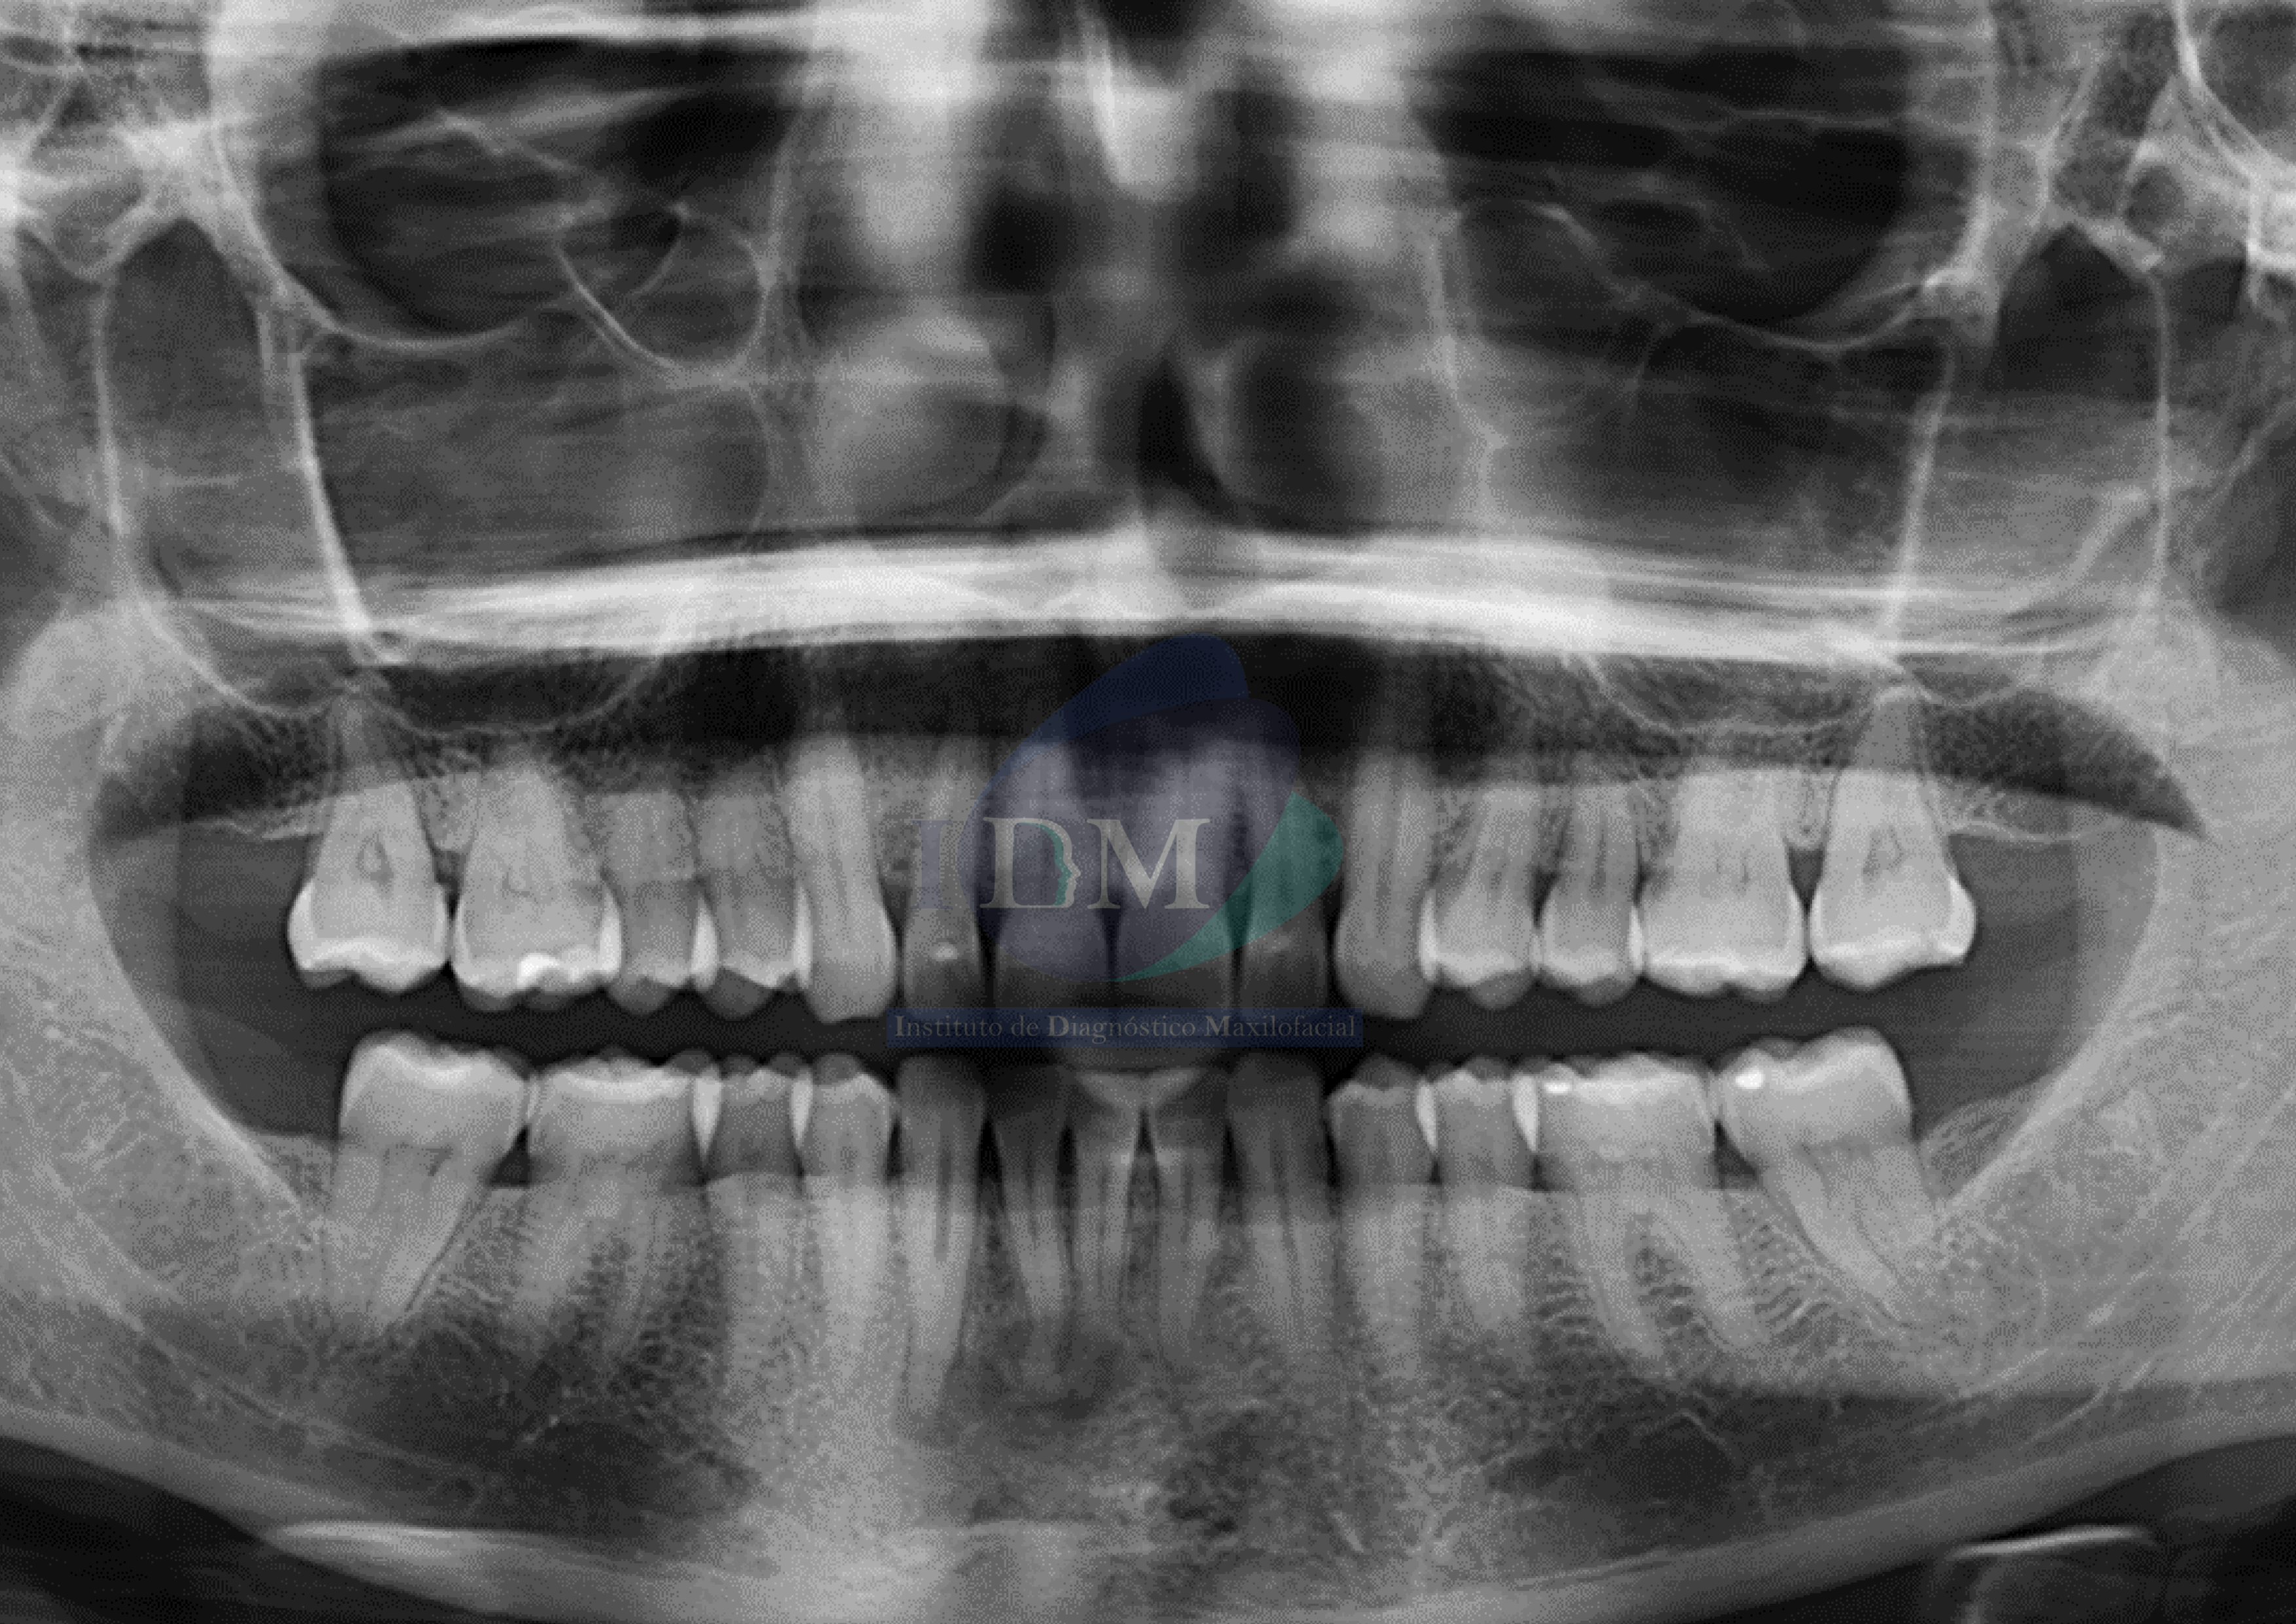

Paciente femenino de 52 años acude al Instituto de Diagnóstico Maxilofacial (sede Miraflores) para evaluación de zona anteroinferior.

Radiografia Panorámica

A la evaluación de la radiografía panorámica se evidencian múltiples imágenes mixtas y de forma irregular en zona apical de las piezas 41, 42 y 43.